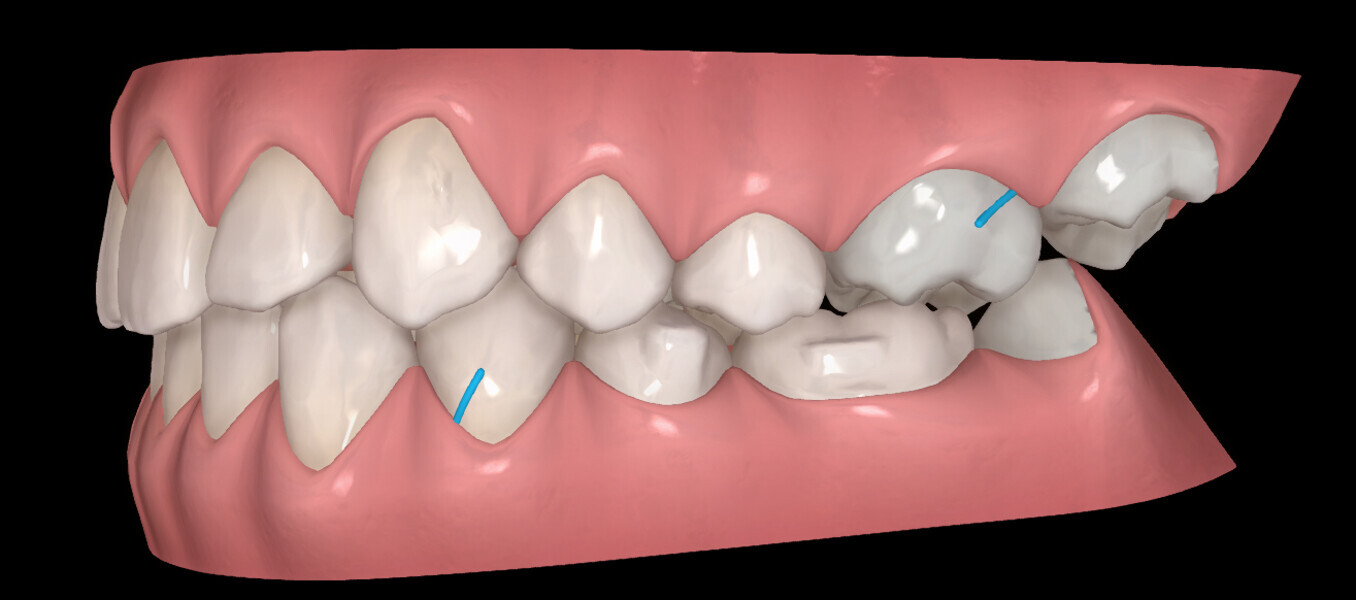

The digital treatment plan (ClinCheck) provided 18 aligners in each arch. The treatment objectives were focused on aligning and levelling the mandibular arch without excessively proclining the mandibular incisors, in order to control the Class III skeletal malocclusion by means of interproximal reduction and slicing of tooth #85. In the maxillary arch, the treatment plan focused on space creation for tooth #13 by distal rotation of the maxillary right molar and mesialisation of the maxillary right lateral incisor simultaneously to centre the midlines. Class II elastics were planned to control distal movement on the right side, and triangular elastics on the high canine were planned on the left side with button cutouts for the aligners. Lateral and posterior maxillary torque were planned to be close to 0° to achieve wider arch design and ideal intercuspation. No digital over-engineering was planned in the set-up, and lingual attachments according to personal preference were placed in the maxillary arch for aesthetic and biomechanical reasons (Figs. 15–19). Eruption compensation for tooth #13 was employed. Because of the age of the patient, the aligners were changed every seven days over the treatment period of less than five months.

At the end of the first stage of aligner treatment (Figs. 20–24), the auxiliary phase began with the bonding of two MTAs on the maxillary right premolars. A 0.016-in Australian archwire, shaped into a cantilever configuration, was then inserted into the MTAs, and a cutout was created on the final aligner. To prevent rotation, the archwire was cinched distal to tooth #15 and the cinch covered with composite.